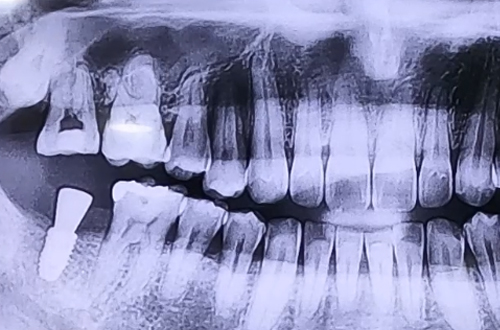

AFTER

본원에서는 다양한 종류의 임플란트를 취급하고 있기 때문에 어떤 임플란트를 사용했든 중단된 치료를 이어서 마무리할 수 있어 꼭 맞는 보철을 제작하여 마무리를 해 드렸습니다.

잇몸이 충분히 단단해진 뒤 뼈이식과 함께 골유착에 용이한 임플란트를 선택하여 진행했어요.

임플란트가 단단히 굳고 보철이 완성되면 진료일지를 통해 다시 찾아뵙겠습니다. ^^